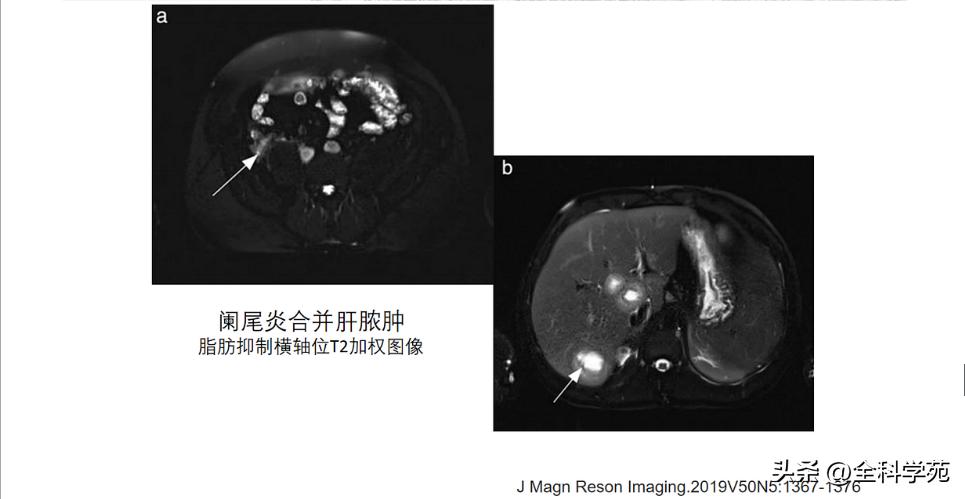

◆ 蜂窝织炎和脓肿 (Phlegmon and abscess

◆ 门静脉炎 (Pylephlebitis)